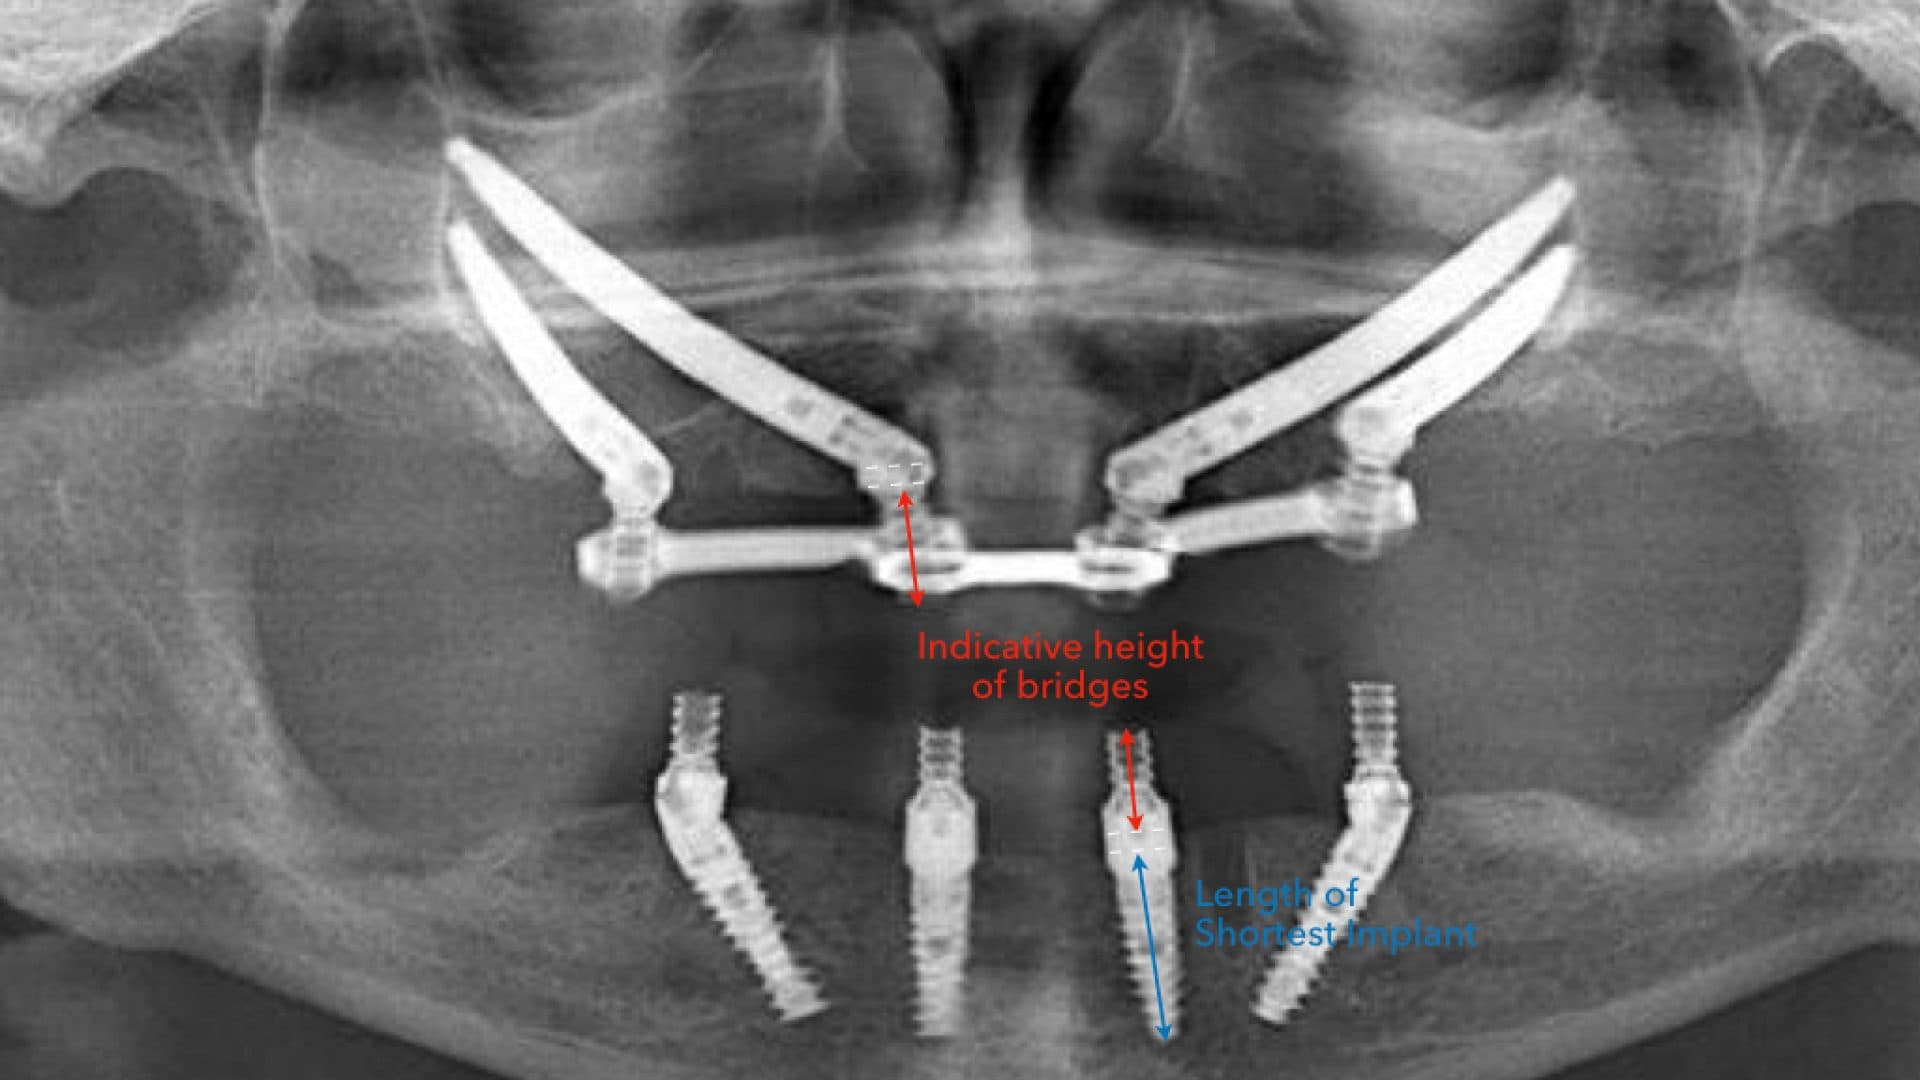

iii. Alignment on x-rays: there should be even spread, rigid connection between the implants, good bone levels, and the height of the prosthesis should be at least as tall as the shortest fixture (See pictures).

Ideal Situation